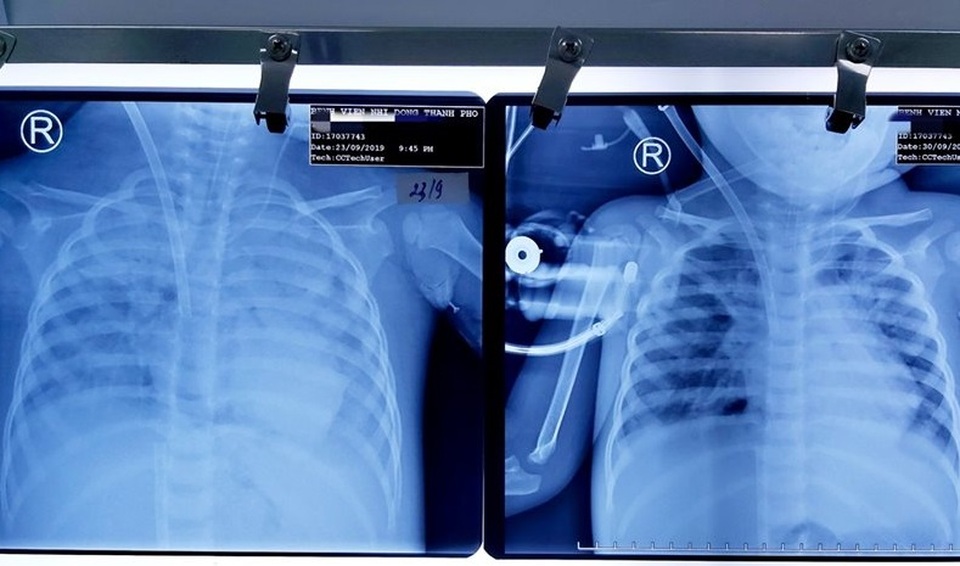

Dù bác sĩ đã sử dụng kháng sinh mạnh kết hợp điều trị tích cực bằng nhiều phương pháp nhưng bé vẫn sốt cao liên tục, viêm phổi nặng dần, sốt co giật, suy hô hấp tiến triển, khởi phát thêm cơn suyễn nặng. Dù được hỗ trợ thông khí áp lực dương liên tục nhưng chức năng phổi suy giảm nghiêm trọng khiến sức thở của bé đuối dần. Trên phim X-quang bác sĩ ghi nhận tổn thương phổi trắng xóa cả 2 bên phổi không thể trao đổi khí thêm được.

Sau hơn 1 tuần điều trị, 2 lá phổi của bé đã được hồi sinh

Kết quả kiểm tra phim phổi cho thấy 2 phế trường sáng dần khắc hẳn với tình trạng phim phổi trắng xóa lúc nhập viện. Tình trạng thông khí tốt cả 2 phổi, hiện bệnh nhân đã có thể tự thở không cần sự hỗ trợ của ECMO. Các bác sĩ điều trị cũng bất ngờ trước sự bình phục kỳ diệu của bé bởi sau khi cai ECMO bệnh nhi không còn cần đến sự hỗ trợ của máy thở. Hệ thống tim phổi nhân tạo là yếu tố then chốt đưa bệnh nhi từ cõi chết trở về giúp bé gần như bình phục hoàn toàn để trở lại cuộc sống bình thường.